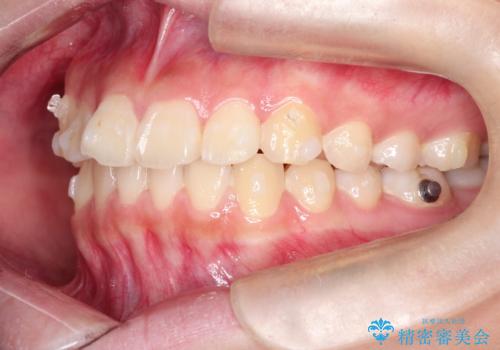

- 前歯が出ているのを主訴に来院されました。

上の前歯が前方に傾斜しており、上の前歯と下の前歯が接触していない状態でした。

上の奥歯を後方に移動させて、前歯を引っ込める計画としました。